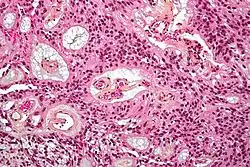

| Micrograph of an ependymoma. H&E stain. | |

Ependymomas are composed of cells with regular, round to oval nuclei. There is a variably dense fibrillary background. Tumor cells may form gland-like round or elongated structures that resemble the embryologic ependymal canal, with long, delicate processes extending into the lumen; more frequently present are perivascular pseudorosettes in which tumor cells are arranged around vessels with an intervening zone consisting of thin ependymal processes directed toward the wall of the vessel.[5]

The World Health Organization classifies ependymomas as Grade I-III. Grade I tumors are low-grade and include the subependymoma subtype, which is more common in adults. Grade II tumors include myxopapillary and conventional ependymoma, which are identified by the presence of perivascular pseudorosettes. Grade III anaplastic ependymomas are the most severe and fast-growing tumors.[4]